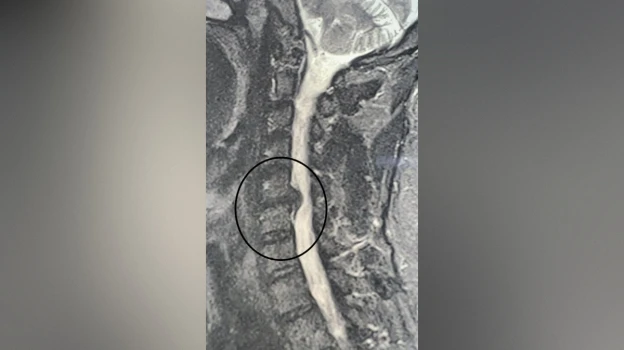

В Воронеже хирурги городской клинической больницы №11 спасли руку пациенту с грыжей. В конце октября в больницу обратился 49-летний мужчина, у которого месяц болела шея. Кроме того, пациент жаловался на онемение и слабость в правой руке. Ранее мужчина проходил лечение, но оно не помогло. Врачи обнаружили грыжу, спондилоартроз (поражение межпозвонковых суставов, которое затрагивает хрящи, костные ткани, связки и околосуставные мышцы. – Прим. ред.) и радикулит. Без удаления грыжи у пациента мог развиться паралич правой руки, поэтому было принято решение провести операцию. Об этом сообщили в пресс-службе министерства здравоохранения Воронежской области во вторник, 18 ноября.

Нейрохирурги Владимир Дронов и Евгений Дронов удалили межпозвонковый диск и грыжу с использованием операционного оптического прибора, микрохирургической техники и инструментария. Помимо этого, была устранена компрессия спинного мозга и нервных корешков, а также установлен межтеловой кейдж – металлическая конструкция, которая размещается между двумя соседними позвонками и соединяет их между собой.